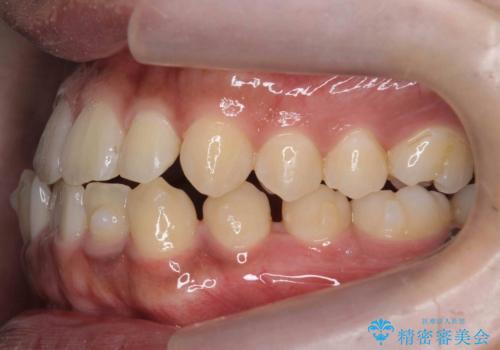

骨格性の受け口 非抜歯で下の歯を後ろに下げる インビザラインで インプラント矯正

- 受け口を主訴に来院。

他院でマウスピース矯正を始めたが、担当医に不信感をもち転院。

治療により受け口が改善し、下あごの輪郭も若干後ろに下がった印象になりました。

当院では下の歯を後ろに下げるため矯正用ミニスクリューを用いてしっかり移動を行う等ご説明をし、治療開始しました。